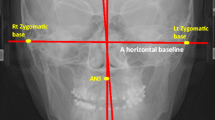

بحسب دراسات حديثة، هناك مؤشرات على أن الخلل في توازن الفك والأسنان قد يكون مرتبطًا بخلل في توازن الجسم ككل، بما في ذلك العمود الفقري.

بمعنى آخر، إذا كان هناك انحراف في الفك أو ميل في وضع الرأس، فقد يتأثر به توازن العمود الفقري تدريجيًا، مما يؤدي إلى ظهور أو زيادة درجة الاعوجاج.

كيف يمكن أن يؤثر الفك على العمود الفقري؟

الجسم يعمل كوحدة متكاملة، فعندما يختل توازن جزء منه، تتأثر بقية الأجزاء لتعويض هذا الخلل.

إذا كان الفك مائلًا إلى أحد الجانبين، فقد يؤدي ذلك إلى ميل في الرأس.

ومع مرور الوقت، يبدأ العنق والكتف في التأقلم مع هذا الميل.

ثم ينتقل التأثير إلى العمود الفقري، الذي يحاول تعديل وضعه للحفاظ على التوازن، مما يؤدي إلى انحناء جانبي بسيط.

ومع استمرار الوضع دون تصحيح، قد يتحول هذا الميل إلى اعوجاج واضح في العمود الفقري.